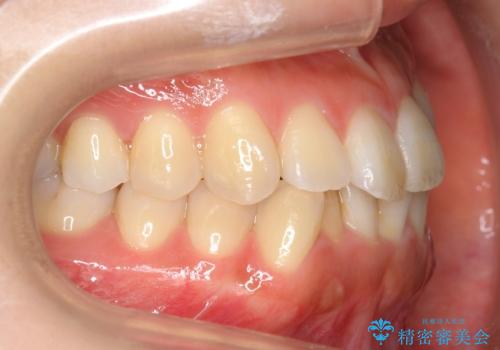

前歯のがたつき インビザラインで 下の奥歯を後ろに下げる

- 上下の前歯のがたつきを主訴に来院。

骨格的に受け口の傾向があり、下の奥歯が前方にに位置しており、下の前歯が特にがたつきが大きい状態でした。

下の奥歯を後ろに下げて下の前歯が前方に出ないように治療しました。

矯正用ミニスクリューを用いて治療しています。

奥歯のかみ合わせの前後的なずれをそのままにして治療すると、前歯が突き上げるような状態になってしまいます。

ただその場で並べるのではなく、症状によっては奥歯を後ろに下げる必要があります。